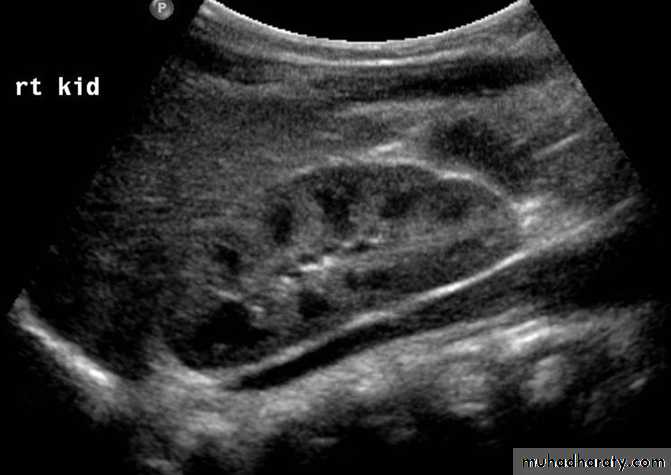

hydronephrosis